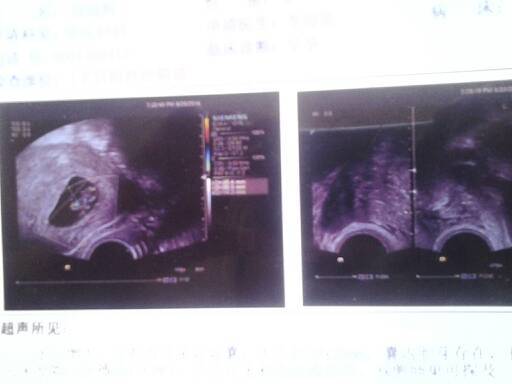

能看出孩子健康不健康吗 能看出孩子健康不健康吗 点击展开 穿貂拿5开路虎& 2014-09-04 16:50 为您推荐: 其他回答 指导意见:你好,只是这个图片是看不出来的,检查的报告及时给医生看就好的,如果有什么情况的医生会告知的 专属于你8 2014-09-04 17:02 相关问题 能帮我看看孩子健康吗? 怀孕几个月可以检查孩子是不是健康的 医生劝我不要这个孩子 这个孩子不健康么?